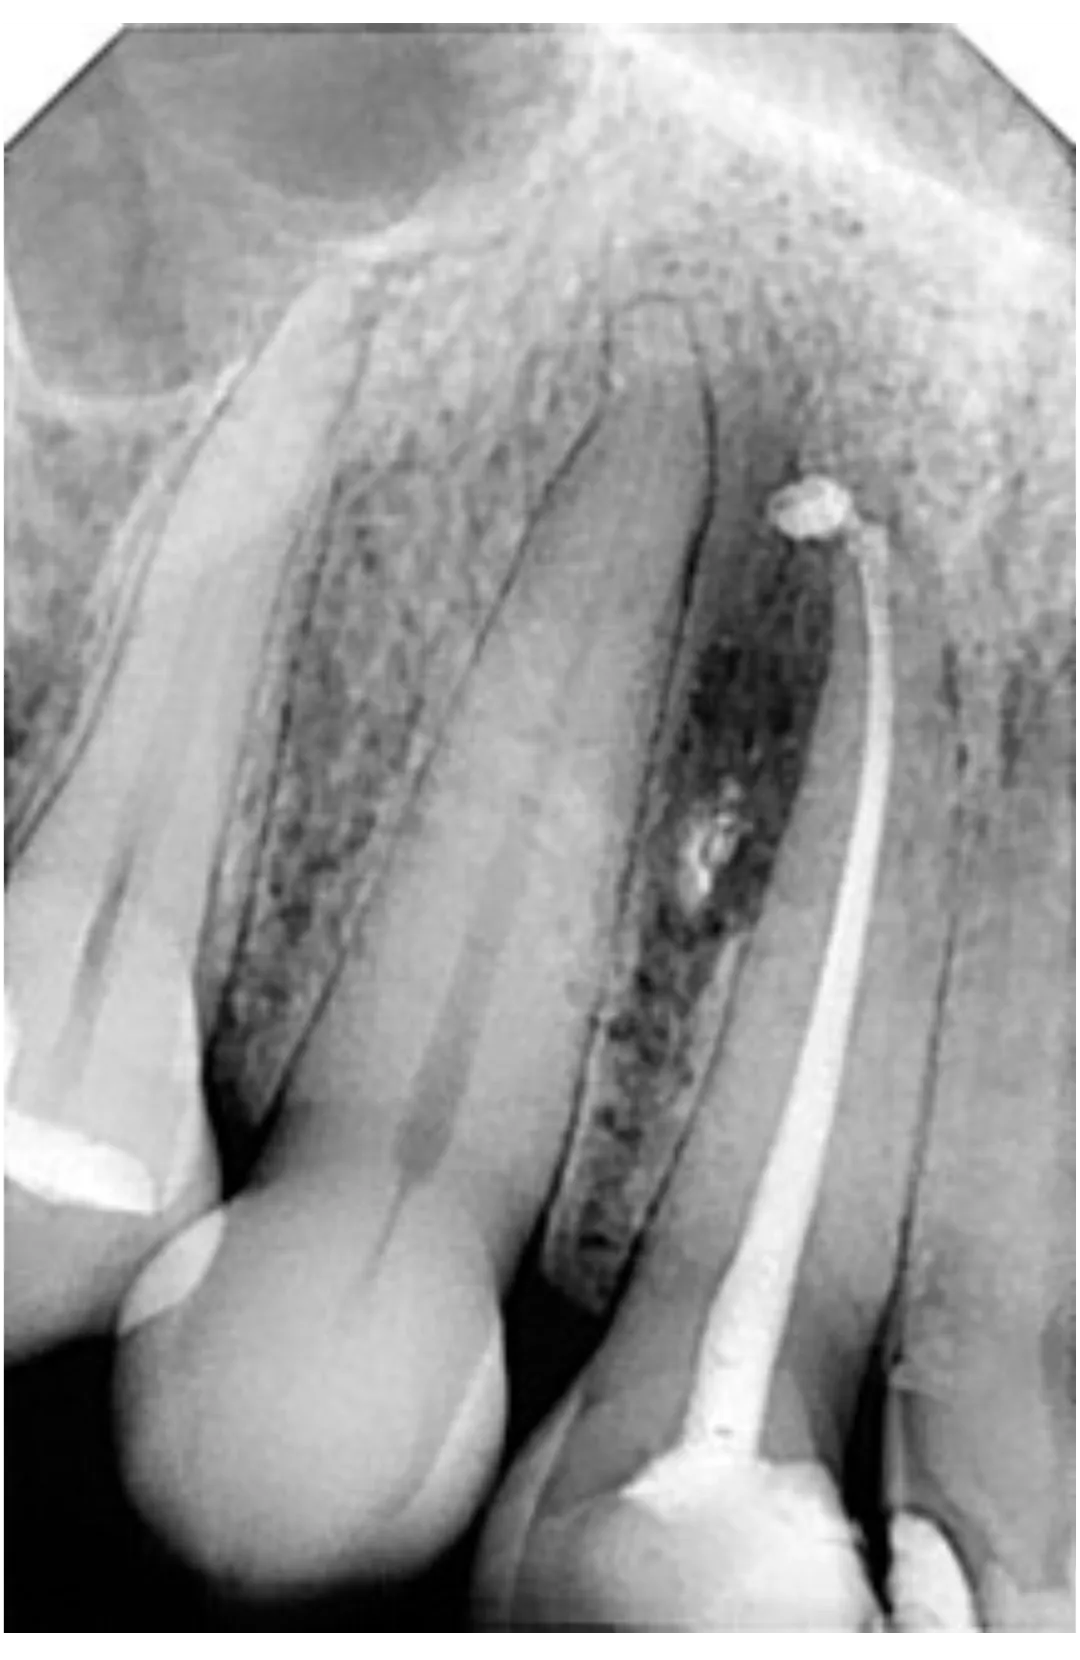

RXDC efikasnost proizlazi iz kombinacije napredne tehnologije i izvanredne sposobnosti za proizvodnju slika visoke definicije. RXDC X- ray uređaj pruža vrhunske performanse, praktičnost i tehnologiju. RXDC se odlikuje generatorom konstantnog potencijala visoke frekvencije (DC) i vrlo malom fokalnom tačkom (0,4 mm) koja omogućava oštre i detaljne slike, istovremeno osiguravajući radnu udobnost i niske doze zračenja za pacijenta.

Veće performanse sa RXDC, rendgenskim uređajem koji kombinuje slike visoke definicije, ergonomski dizajn i niske doze zračenja.

SUPERIORNA DIJAGNOSTIČKA KVALITETA Dobijena u samo nekoliko jednostavnih koraka, sve slike su visoke rezolucije.

NAPREDNA TEHNOLOGIJA

NewTom RXDC rendgenski uređaj visoke frekvencije baziran je na NewTom-ovom znanju, sa udaljenošću izvora od 30 cm i fokalnom tačkom od 0,4 mm.